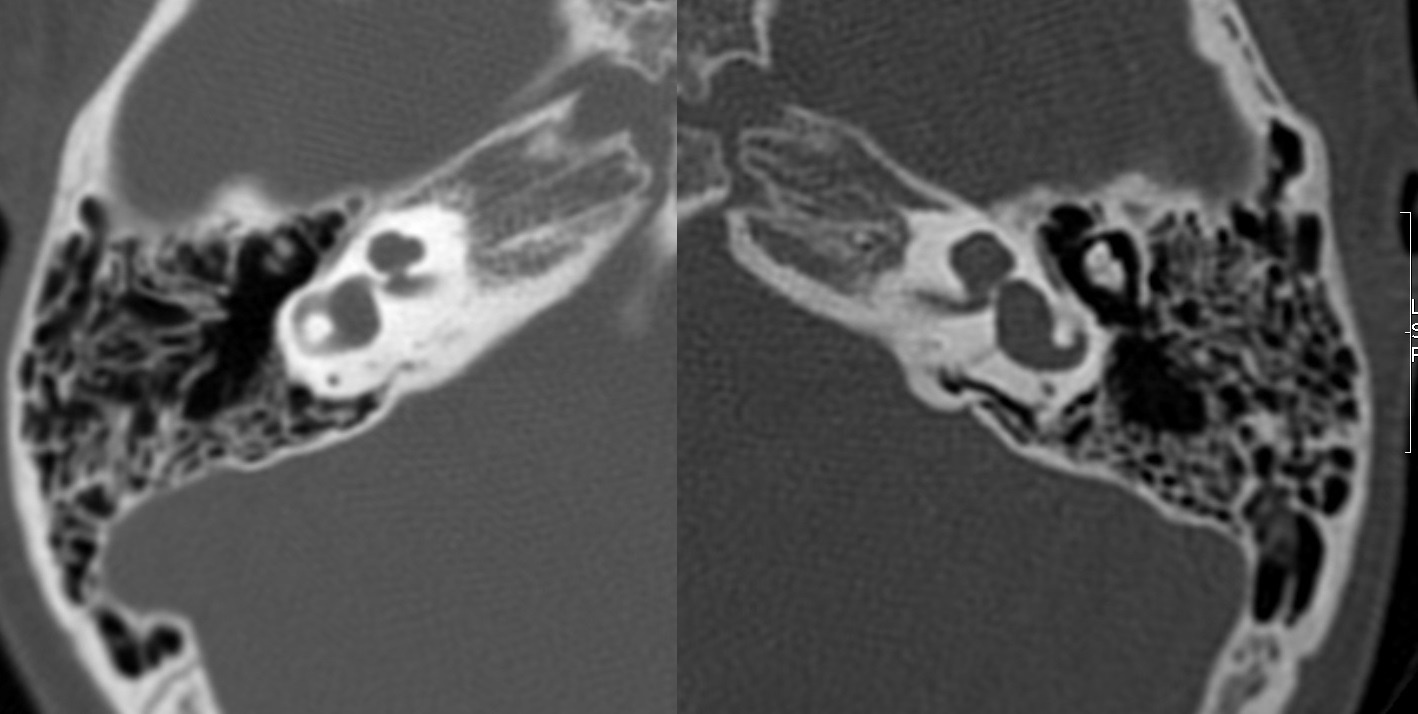

Evaluación de Imagen (TC)

Los hallazgos radiológicos, mediante TC de oídos a cuatro pacientes varones y una madre oyente, portadora obligada, se analizaron y clasificaron según Sennanoğlu et al. [8,9]. En ese sentido, son consistentes con PI-III en tres de ellos: IV-1, IV -2 y IV- 4. El paciente IV-3 mostró PI-I; la madre portadora obligada no mostró alteración alguna (Ver Tabla 3). En los cuatro pacientes estudiados de esta familia observamos dos tipos de MOI, PI-I y PI-III, incluso entre los hermanos IV-2 y IV-3, que presentaron diferente tipo de PI, lo que evidencia expresividad variable. La malformación PI-III es de las MOI menos frecuente y se encuentra presente en este estudio familiar como predominante.

| IV-1 | Ausencia de modiolo con presencia bilateral de septo interescalar | Discretamente amplio | Dilatación parcial en su segmento lateral | PI-III | Imagen 7 |

| IV-2 | De tipo quístico con ausencia bilateral de modiolo | Dilatado con hipoplasia de CSL izquierdo | Aparente estenosis de la entrada del nervio coclear al miodolo | PI-III | Imagen 8 |

| IV-3 | Ausencia de modiolo con presencia bilateral de septo interescalar | Dilatación en su segmento lateral | PI-I | Imagen 9 | |

| IV-4 | Ausencia de modiolo con presencia de septo interescalar bilateral | Discretamente amplio | Dilatación en su segmento lateral | PI-III | Imagen 10 |

| III-2 | Normal | Normal | Normal |

Abreviaturas: MOI: Malformación de oído interno; PI-III: partición incompleta de cóclea Tipo III; CSL: canal semicircular lateral; PI-I: partición incompleta de cóclea Tipo I.

| IV-2 | HNS profunda bilateral con curvas de perfil plano, congénita | PI-III | 4 y 8 |

| IV-3 | HNS media bilateral congénita | PI-I | 1, 2 y 9 |